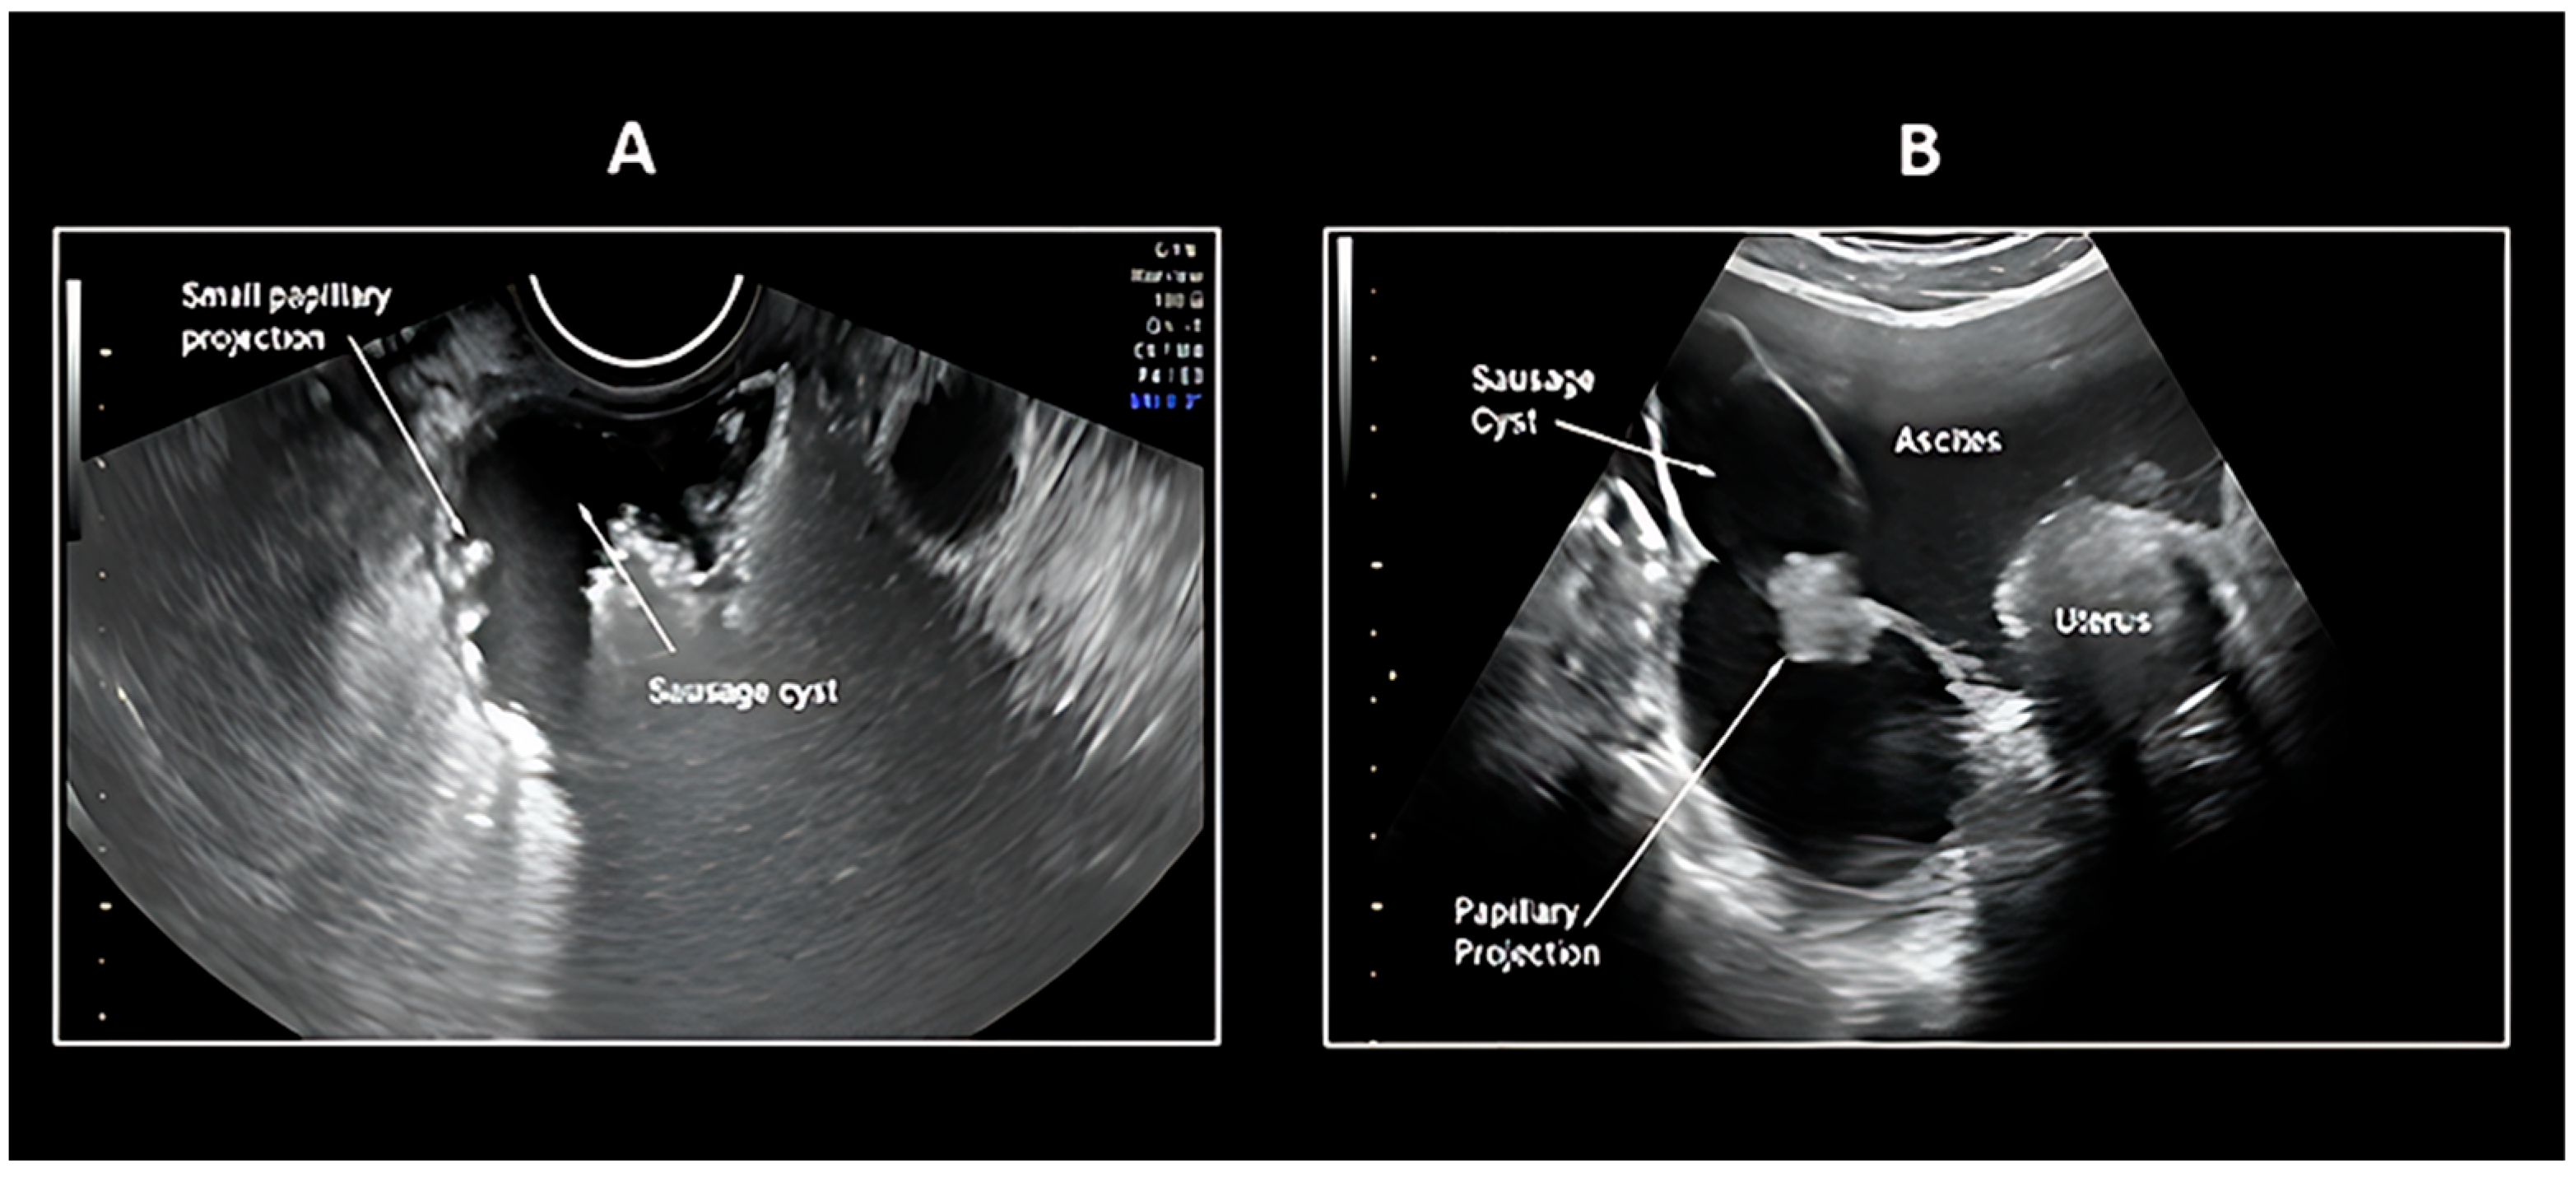

5.1. Transvaginal Ultrasonography

- Tongsong, T.; Wanapirak, C.; Tantipalakorn, C.; Tinnangwattana, D. Sonographic Diagnosis of Tubal Cancer with IOTA Simple Rules Plus Pattern Recognition. Asian Pac. J. Cancer Prev. APJCP 2017, 18, 3011–3015. [Google Scholar]

| Morphology | Tubular/sausage-shaped mass |